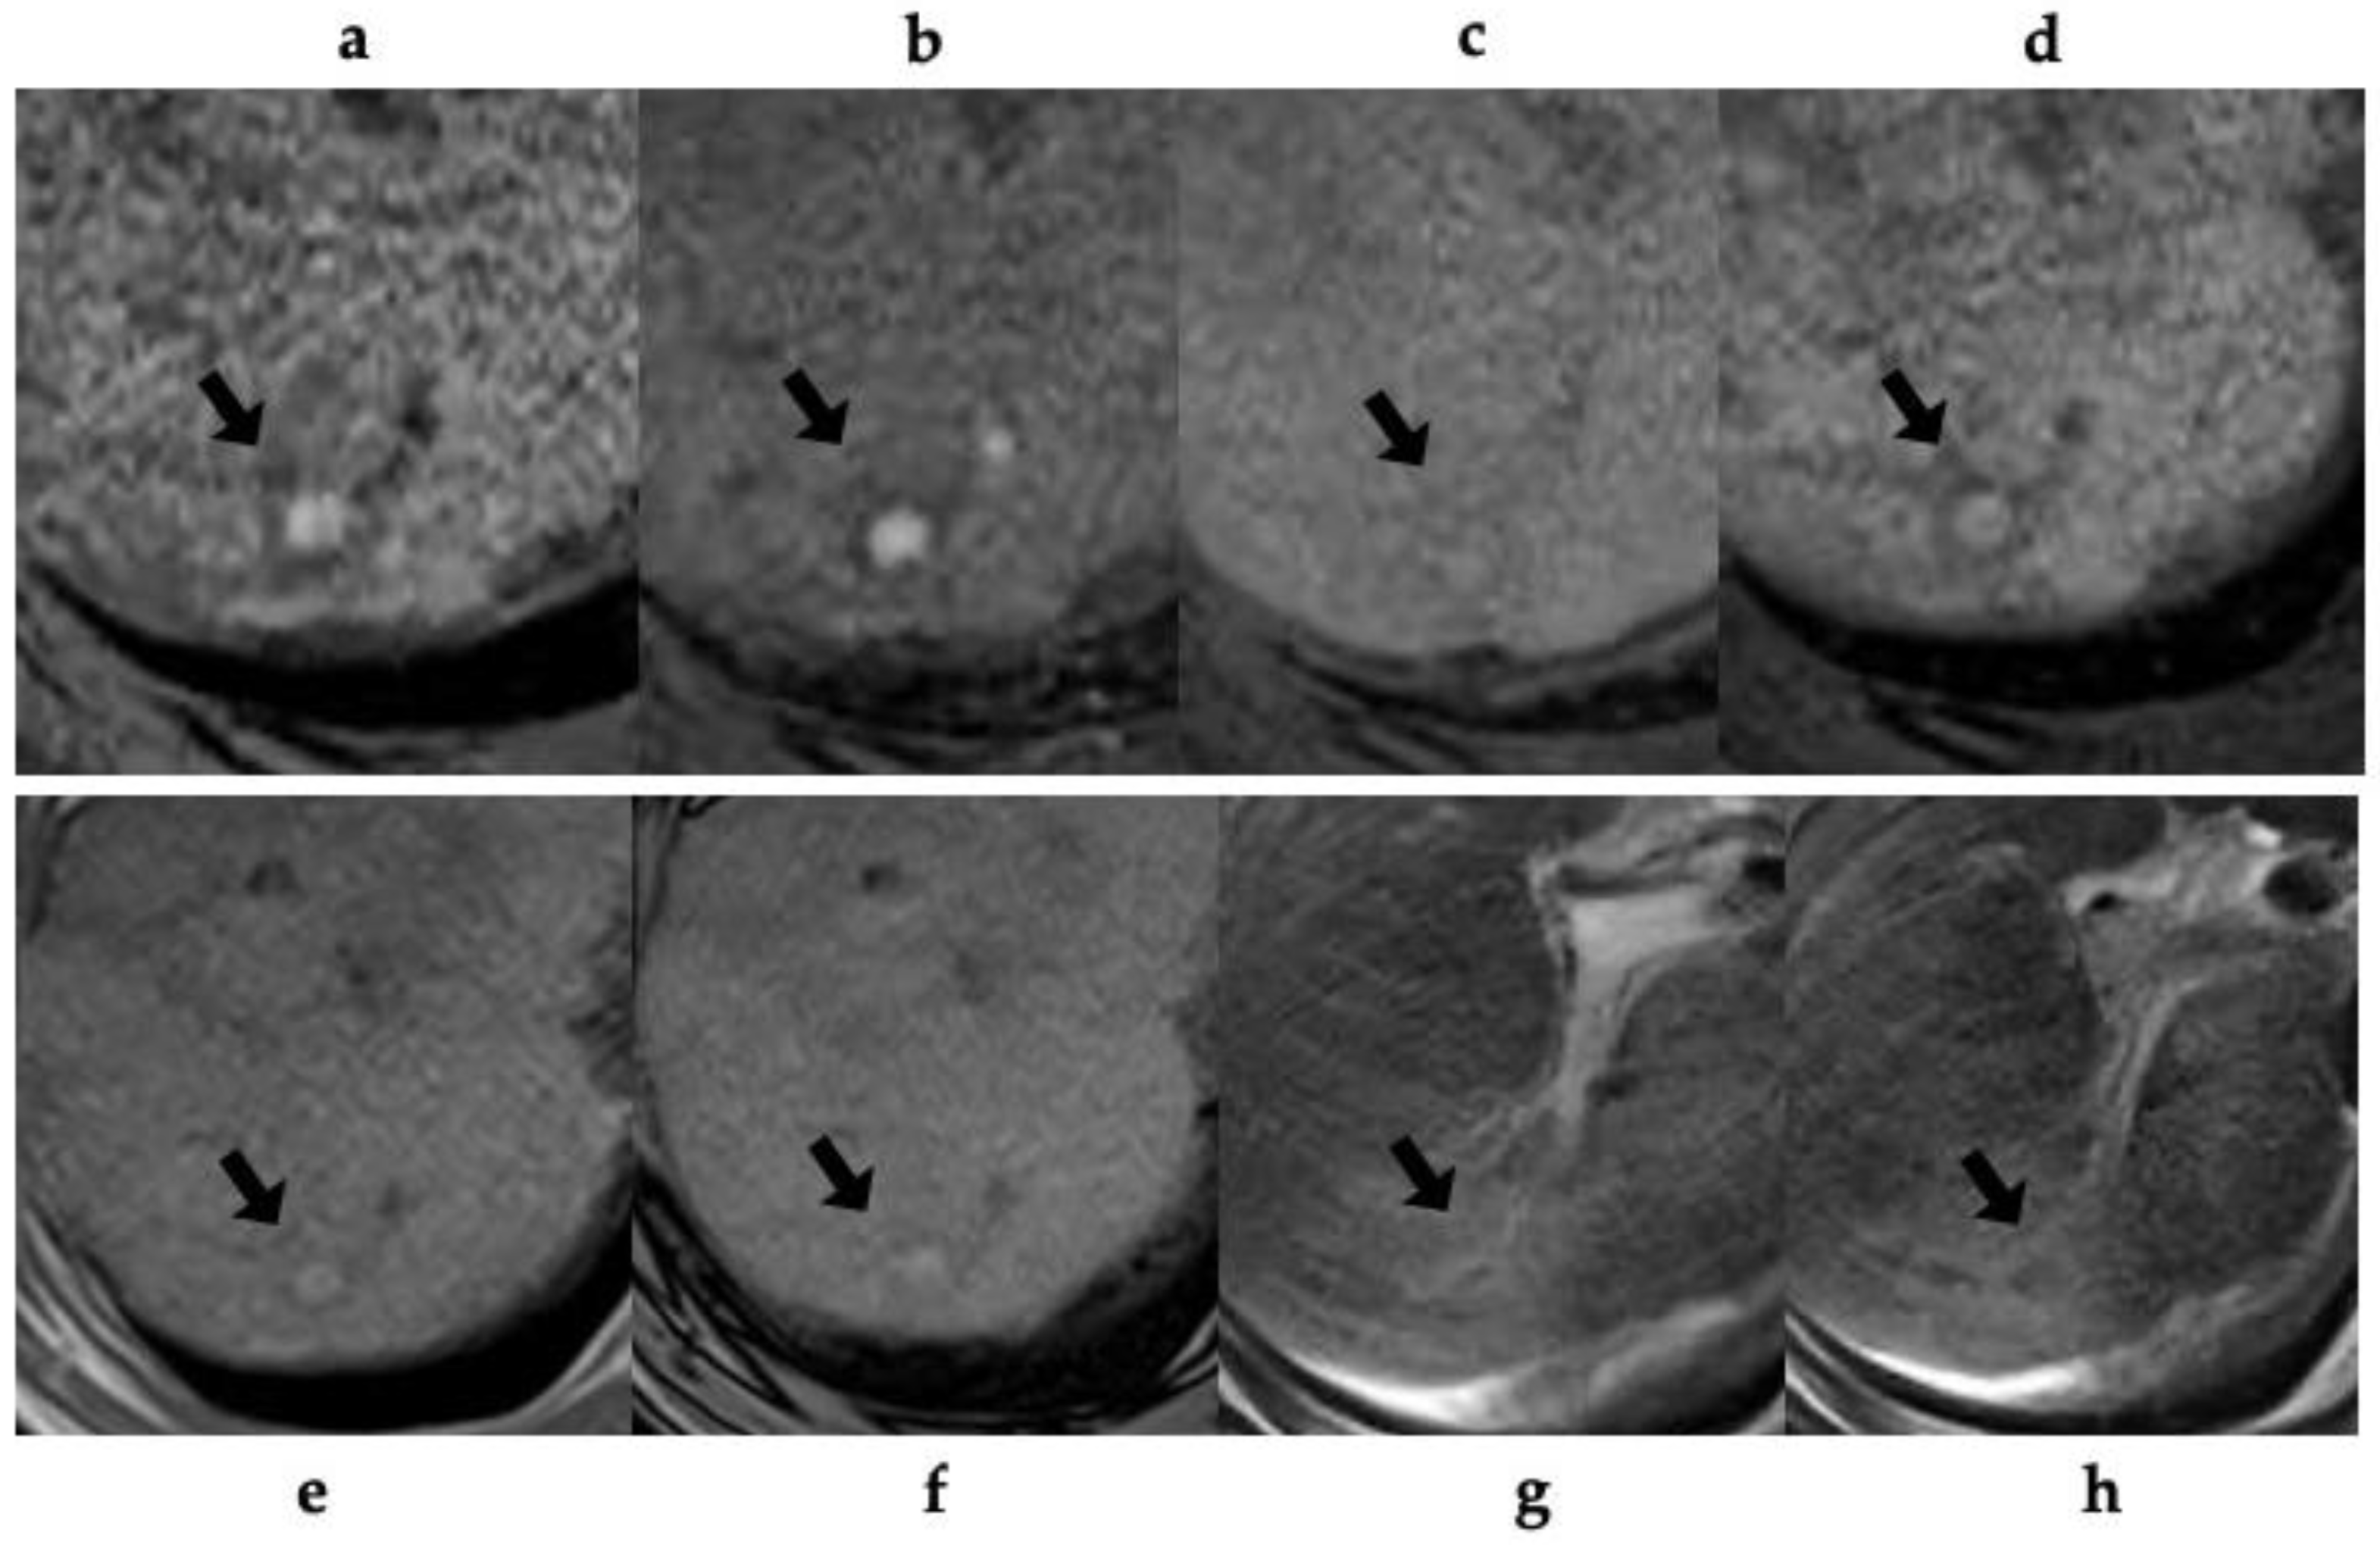

Figure 3. A 65-year-old man with alcoholic liver cirrhosis (patient no. 8). (a-b) T1-weighted gradient-echo (GRE) MR (a; in-phase, b; opposed-phase) image shows a small and high-signal-intensity nodule (arrow) in segment 7 of the liver. (c) pre-contrast T1-weighted GRE MR imaging shows iso-slightly high-intensity nodule (arrow). Gadoxetic acid-enhanced T1-weighted GRE MR imaging obtained during the (d) arterial- and (e) portal-venous phase reveal a nodule with arterial phase hyperenhancement (arrow) and without washout (arrow). (f) The hepatobiliary phase of the gadoxetic acid-enhanced T1-weighted GRE MRI shows homogeneous high-intense uptake (arrow). (g) T2*-weighted GRE MR image shows iso-intensity nodule (arrow). (h) The SPIO-enhanced T2*-weighted GRE MR image shows the lesion as a low-signal intensity nodule (arrow) with SPIO-uptake compared with the surrounding liver parenchyma.

Table 3 shows the MRI findings of the FNH-like lesions. Among the thirteen patients with FNH-like lesions, eleven (85%) showed high or iso-high intensity on T1WI, seven (54%) showed iso-high intensity on T2WI, six (46%) showed low intensity, three (23%) showed high-intensity central scars, and 10 (77%) showed no central scars on T2WI. Chemical shift artefacts were observed in all the 13 patients with FNH-like lesions (Figure 1 and Figure 2). In the six patients who underwent gadoxetic acid-enhanced MRI (Figure 3 and Figure 4), all lesions exhibited marked homogeneous enhancement during the arterial phase. Two enhancement patterns were observed on the HBP: heterogeneous hyperintense (n = 3, 43%) and ring-like enhancement (n = 4, 57%). In the eight patients who underwent SPIO-enhanced MRI, all lesions exhibited a marked homogeneous uptake pattern on post-SPIO-enhanced MRI (Figure 1 and Figure 3).